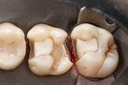

Photos of Clinical Operations

Drs. Peter Kearney, Terry McKay, John St. Germain, and Laurie Vanzella - Mentors